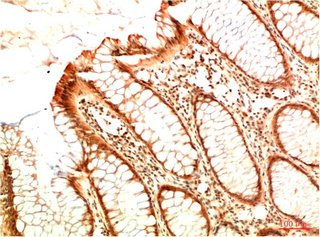

• Immunohistochemical analysis of paraffin-embedded Human Colon Carcinoma Tissue using Acetyl P53(K382) Mouse mAb diluted at 1:200.